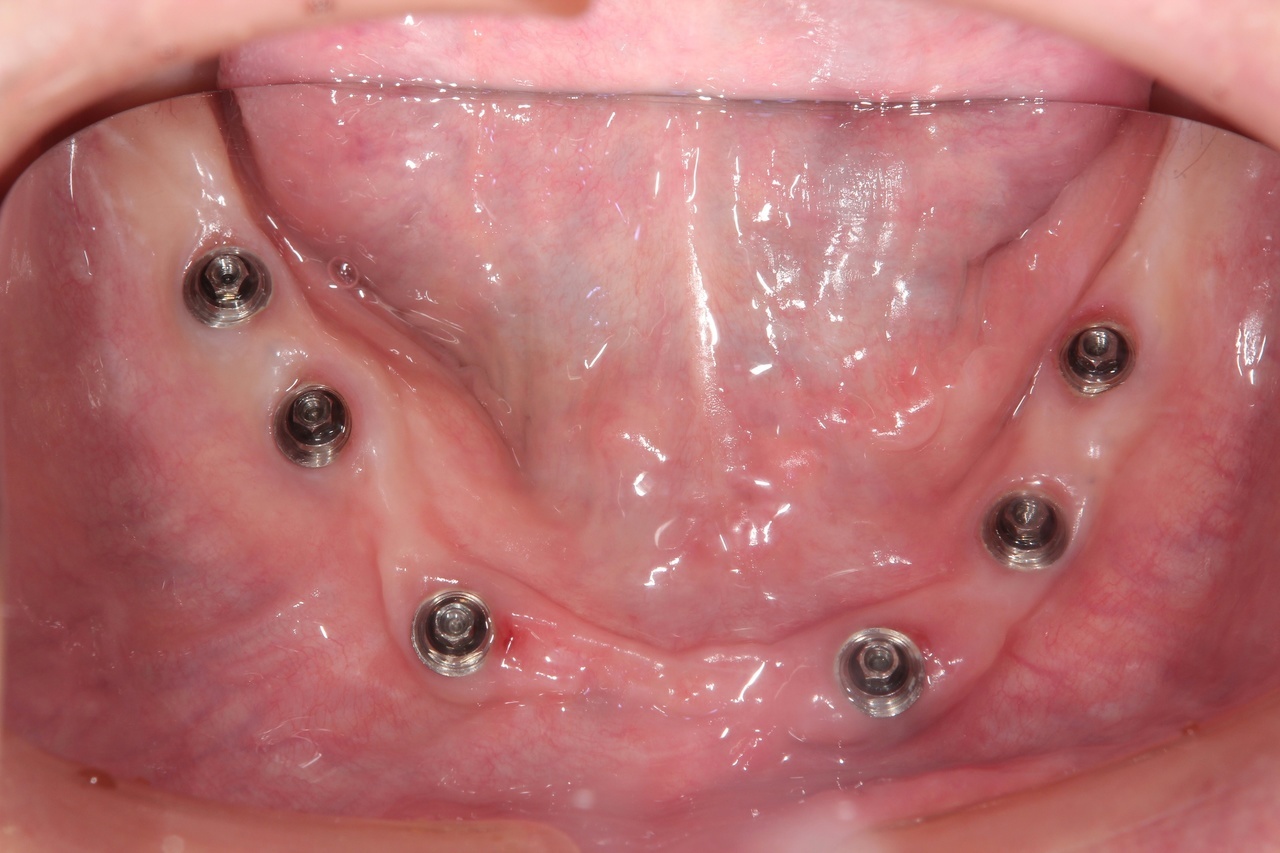

インプラントオーバーデンチャー<ロケータータイプ> (沼津市在住 男性)

インプラントを埋め込み、固定用のロケーターを装着し、入れ歯をしっかりと固定する治療法です。

少ない本数でがっちり噛める治療法です。取り外し可能でしっかり固定できるので、入れ歯の誤飲の心配がなく、手入れがしやすいので寝たきりになっても安心に使用出来ます。

しっかり噛むことで踏ん張りがきくので転んで骨折するリスク回避にもなります。

● オーバーデンチャーを外した状態

● オーバーデンチャーを付けた状態

インプラント4本+入れ歯:2,100,000円+税

静脈内鎮静法:0円

上顎と下顎に、インプラント4本+入れ歯、を作る場合 総額:4.200.000+税

骨の条件が良ければ、下顎の場合はインプラントの本数を減らすことができます。

【インプラント2本+入れ歯】1,550,000円+税

【インプラント3本+入れ歯】1,825,000円+税